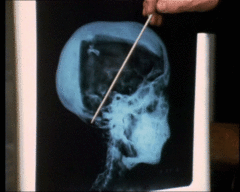

قبل هذا التقرير كانت هناك محاولات لمعرفة سبب الموت باستعمال أشعة أكس X-rays على مومياء توت عنخ أمون جرت في جامعة ليفربول و جامعة ميشيغان في 1968 و عام 1978 على التوالي وتوصلت الجامعتان إلى اكتشاف بقعة داكنة تحت جمجمة توت عنخ أمون من الخلف والذي تم تفسيره كنزيف في الدماغ مما ادى إلى انتشار فرضية انه قد تلقى ضربة في رأسه ادت إلى نزيف في الدماغ ثم الموت

لفترة طويلة كان سبب وفاة توت عنخ أمون مسألة مثيرة للجدل وكانت هناك الكثير من نظريات المؤامرة التي كانت ترجح فكرة انه لم يمت وانما تم قتله في عملية اغتيال. في 8 مارس 2005 ونتيجة لإستخدام التصوير الحاسوبي الشريحي الثلاثي الأبعاد three-dimensional CT scans على مومياء توت عنخ أمون صرح عالم الأثار المصري زاهي حواس انه لاتوجد اية ادلة على ان توت عنخ أمون قد تعرض إلى عملية اغتيال واضاف ان الفتحة الموجودة في جمجمته لا تعود لسبب تلقيه ضربة على الرأس كما كان يعتقد في السابق وانما تم احداث هذه الفتحة بعد الموت لغرض التحنيط وعلل زاهي حواس الكسر في عظم الفخذ الأيسر الذي طالما تم ربطه بنظرية الأغتيال بانه نتيجة كسر في عظم الفخذ تعرض له توت عنخ أمون قبل موته وربما يكون الألتهاب الناتج من هذا الكسر قد تسبب في وفاته.